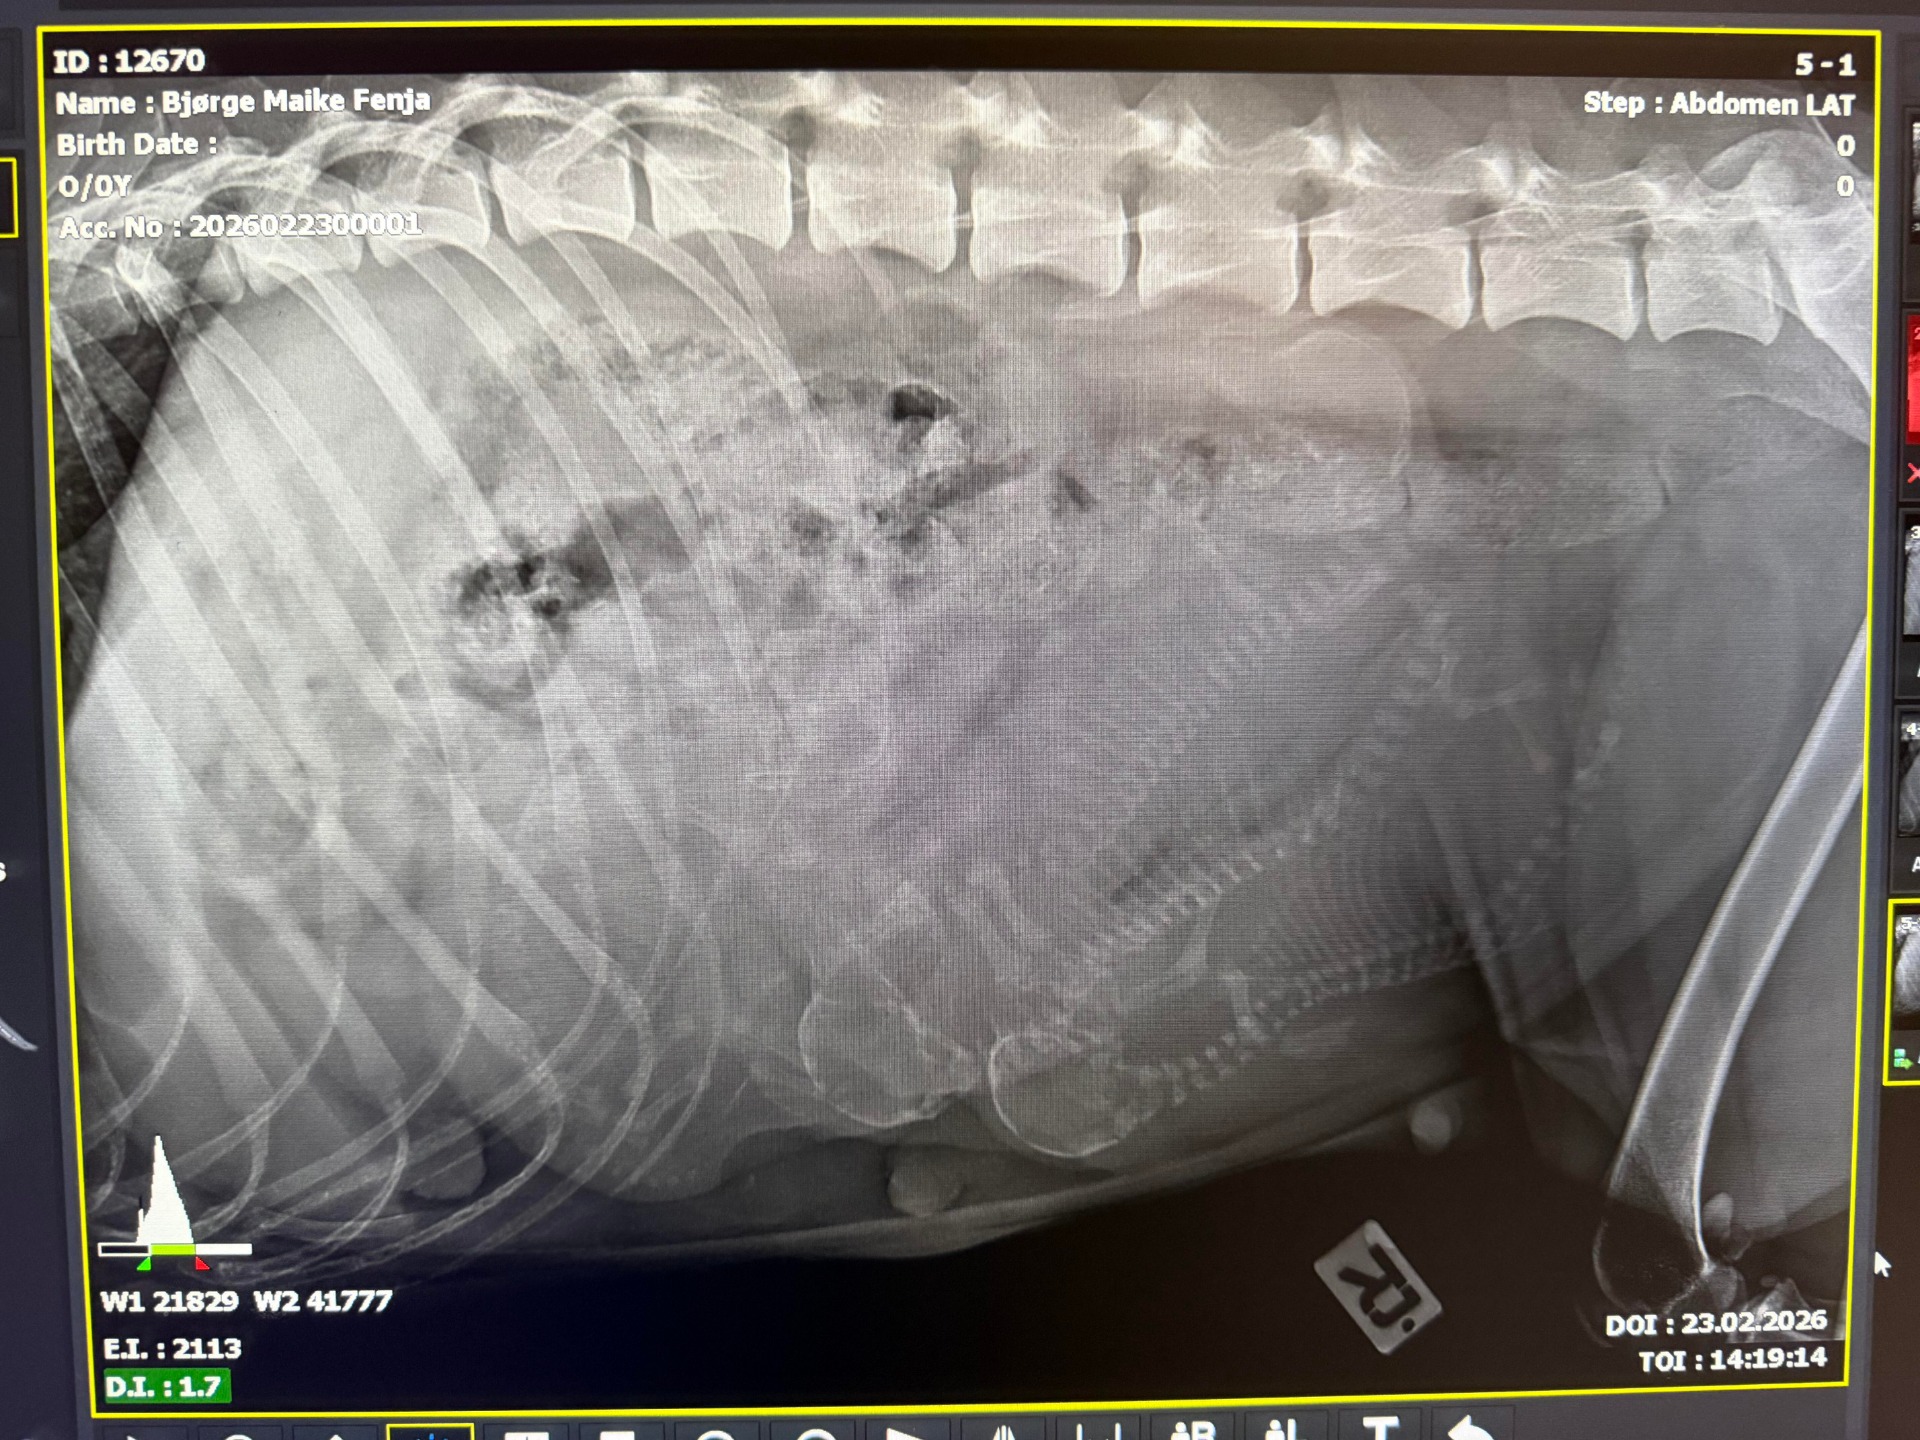

Valpene vokser i magen til Fenja og nå har vi også det første bildet av A-kullet!